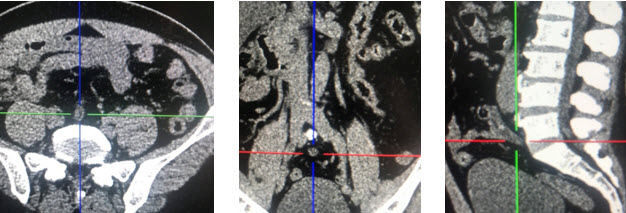

8h18 ngày 25/4/2020 mời ngoại tổng hợp hội chẩn với chẩn đoán tắc ruột. Thăm khám ghi  nhận: đau tức thượng vị và quanh rốn, không sốt,  nôn khan, bụng chướng vừa, chưa trung, đại tiện, không có điểm đau khu trú, hố chậu phải không đau. hình ảnh Xquang không nghĩ đến tắc ruột- cảnh giác VRTC, hẹn khám lại sau 3 giờ. Sau 3 giờ thăm khám lại thấy bệnh nhân có phản ứng vùng hạ vị nghi ngờ 1 tình trạng VRTC tiểu khung. chỉ định siêu âm lại với chẩn đoán VRTC tuy nhiên kết quả siêu âm chỉ cho biết: các quai ruột ứ đọng dịch và phân, giảm nhu động, có ít dịch giữa các quai ruột, ruột thừa hạn chế khảo sát. Bệnh nhân được chỉ định mổ cấp cứu với chẩn đoán VRTC tiểu khung. Tuy nhiên để khẳng định thêm chẩn đoán chúng tôi hội chẩn qua PACS (một phương tiện đọc phim online mà bệnh viện chúng tôi đang sử dụng) hình ảnh CT ổ bụng không tiêm thuốc cản quang ngày 24/4/2020 phát hiện ruột thừa nằm giữa ổ bụng, lòng giảm tỷ trọng, đường kính 10mm, có sỏi phân. Kết luận: VRTC nằm giữa ổ bụng.

2020 05 07 10 52 30

Hình 2. Hình ảnh CT scan 24.4.2020

Trong trường hợp của chúng tôi manh tràng đi vào giữa ổ bụng khiến ruột thừa nằm giữa ổ bụng gây nên các triệu chứng không điển hình như đã mô tả. lần theo manh tràng chúng tôi bắt gặp cấu trúc hình ống đường kính 10mm, thành phù nề, có sỏi phân. Đây là các dấu hiệu có thể kết luận chẩn đoán VRTC. Đây là lợi ích vượt trội của CT so với siêu âm trong chẩn đoán các bệnh lý trong ổ bụng, đặc biệt là các bệnh lý ruột non và đại tràng. CT có thể giúp chúng ta tìm ra manh tràng và đại tràng lên bằng cách lần theo các quai ruột non. CT cũng có thể phân biệt ruột già và ruột non bằng cách chỉ ra các van conniventes hay haustrae. Trong trường hợp ruột quay bất toàn dẫn đến ruột thừa nằm ở vị trí bất thường, CT sẽ giúp ích cho chẩn đoán bằng cách chỉ ra mối quan hệ giữa động mạch và tĩnh mạch mạc treo tràng trên [3]. Như vậy CT là một phương tiện hữu hiệu để chẩn đoán VRTC khi ruột thừa ở các vị trí bất thường như trong trường hợp đảo ngược phủ tạng, ruột quay bất toàn hay manh tràng quá di động như trong trường hợp của chúng tôi.